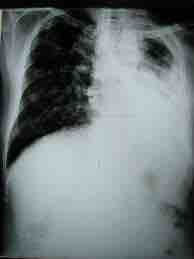

Tuberculosis

This x-ray of a tuberculosis patient shows the lung on the left side completely infected and the right lung partially infected (the dark areas), with tuberculosis.